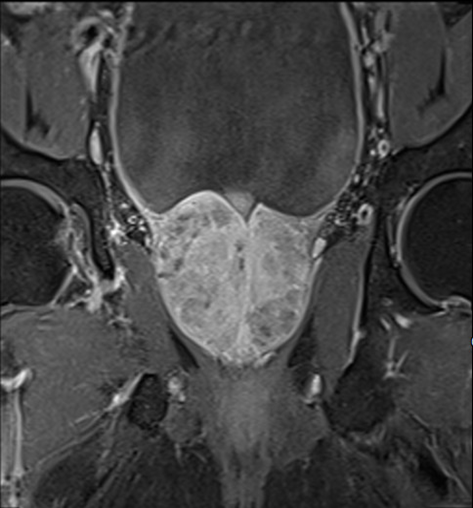

Bệnh nhân là ông Peter Trương (58 tuổi, Việt kiều Mỹ). Nhập viện vào cuối tháng 10 trong tình trạng bí tiểu, bệnh nhân được các bác sĩ chỉ định siêu âm bụng, chụp cộng hưởng từ vùng chậu có tiêm thuốc tương phản và kết hợp các xét nghiệm cần thiết để đánh giá tình trạng bệnh đồng thời loại trừ nguy cơ ác tính. Kết quả chụp cộng hưởng từ cho thấy thể tích tuyến tiền liệt của người bệnh là 81 ml (người bình thường chỉ khoảng 25 ml).

Hình ảnh chụp cộng hưởng từ cho thấy tiền liệt tuyến phì đại (mặt cắt đứng dọc và đứng ngang), lồi vào lòng bàng quang, thể tích khoảng 81 ml. |